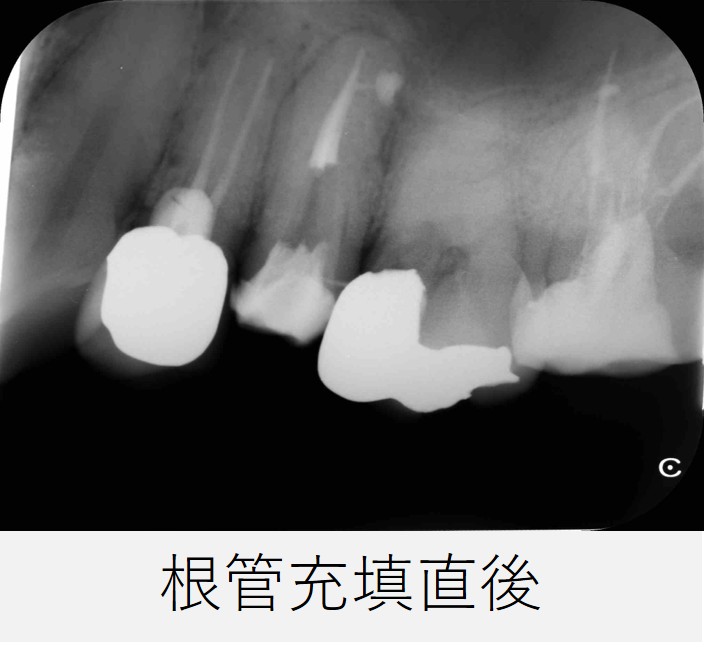

- レントゲンを撮影し、根管充填の状態が良好であることを確認しました。

根管充填後から6カ月

- レントゲンおよびCTで確認したところ、根の先や側面に見られていた透過像は縮小し、骨の回復傾向が確認されました。